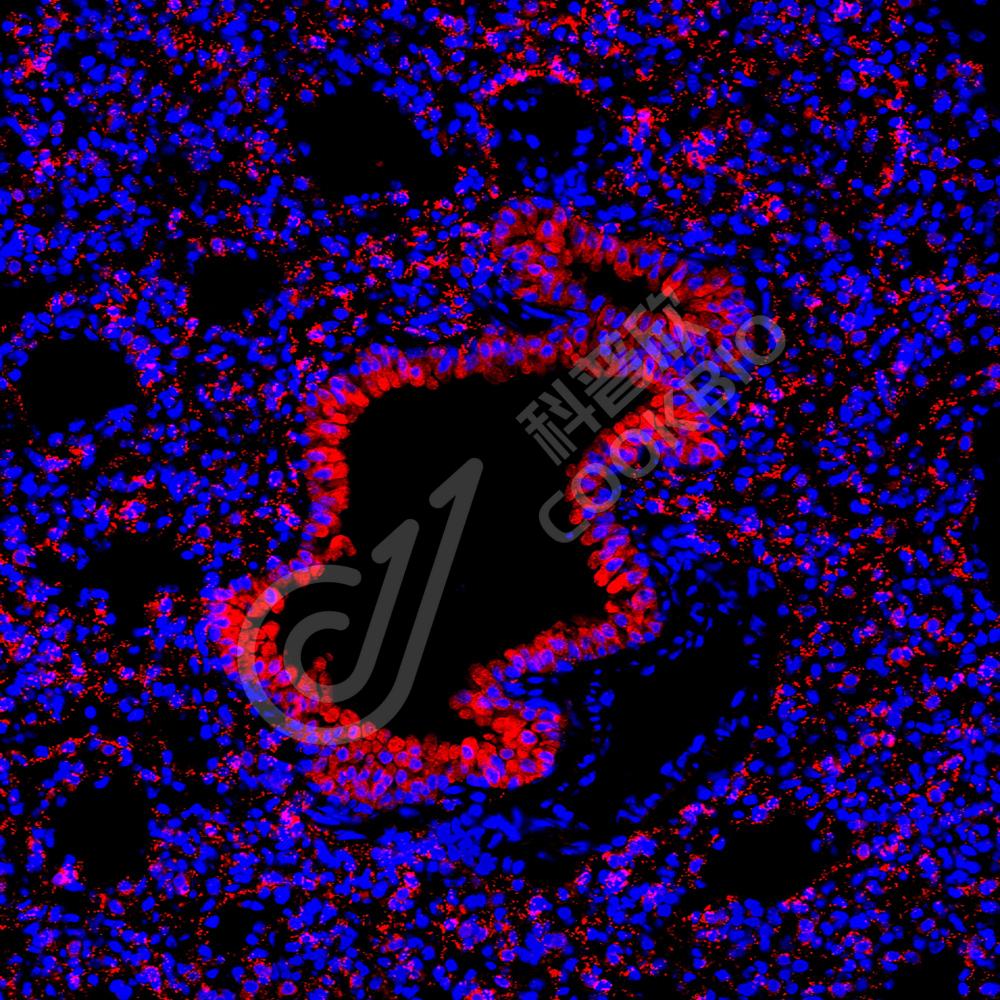

IHC检测14-3-3 zeta蛋白(货号 K1333069).

样品: 大鼠脑, 4%多聚甲醛 (货号KSG1101) 固定12-24小时.

抗原修复: 柠檬酸抗原修复液(干粉, pH 6.0) (KSG1201), 98℃, 20分钟.

—抗: 1: 1300稀释, 4℃ 孵育过夜.

二抗: S-vision免疫组化多聚二抗(山羊抗兔),即用型 (货号KB3906), 室温孵育20分钟.